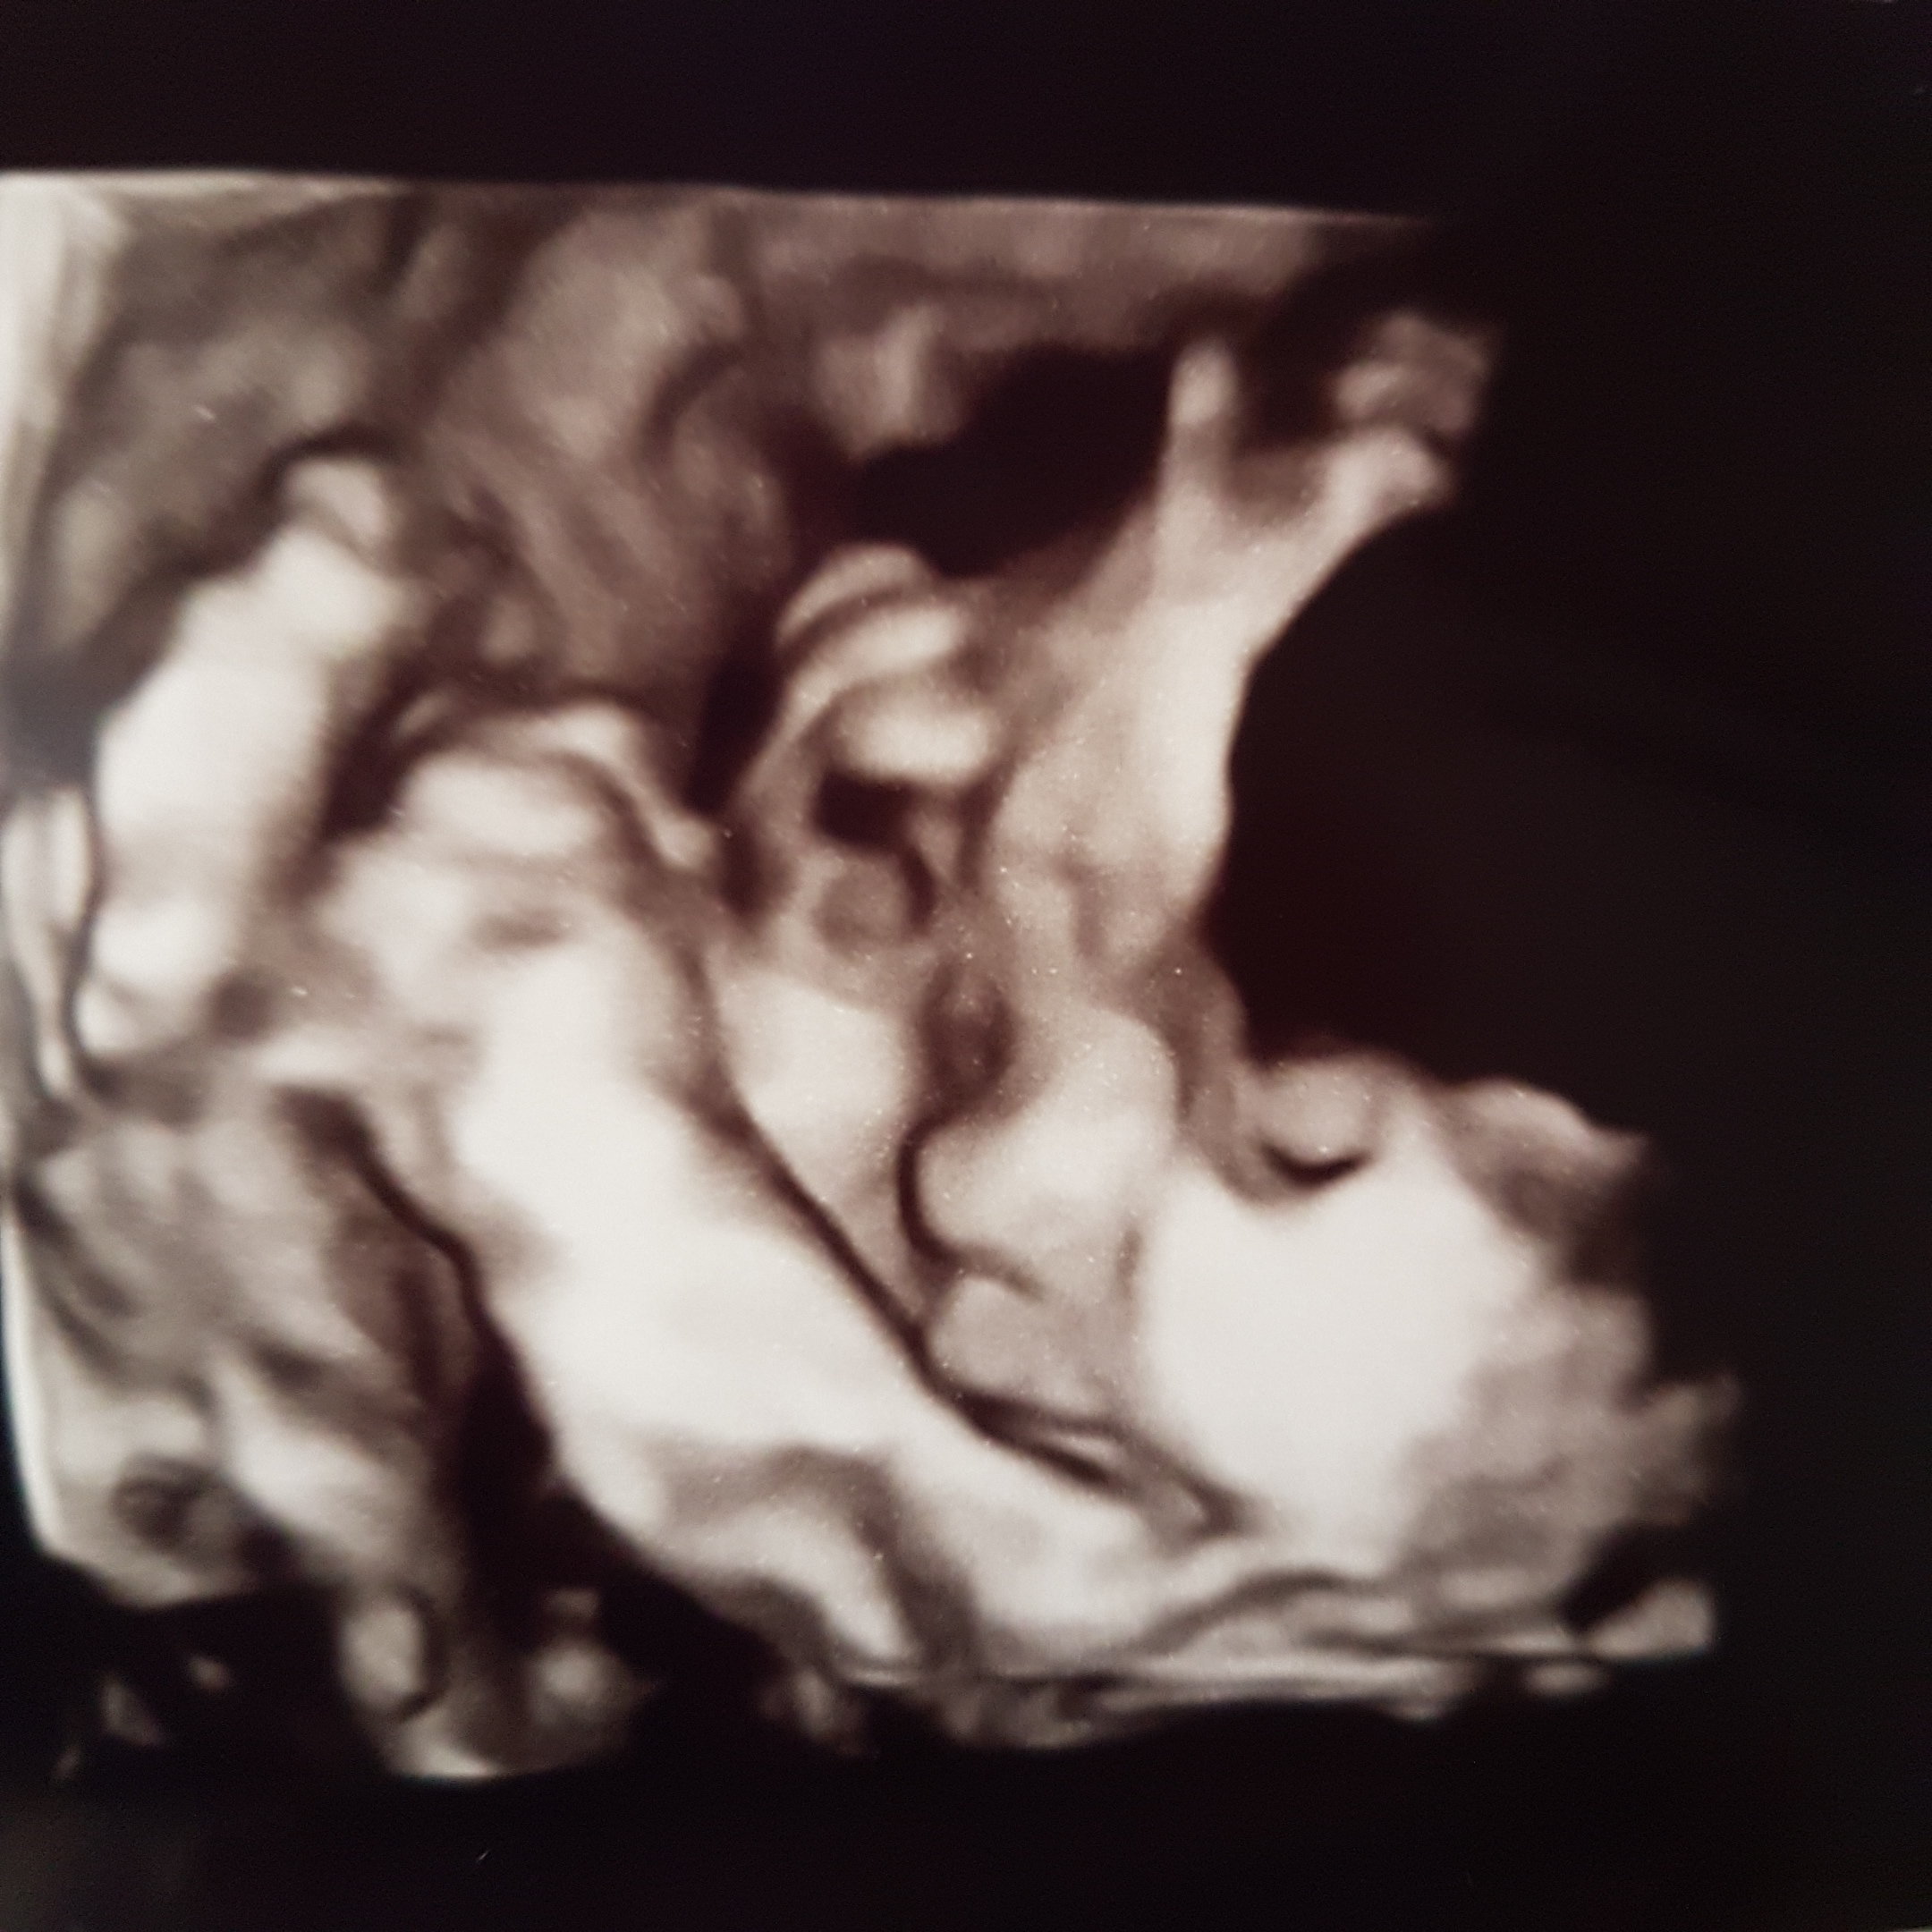

Melduję się po wizycie. Synek waży 1103g zdrowiutki chlopak. Jak narazie ułożony jest główka do góry,ale ma jeszcze czas i miejsce żeby się przekręcić. Wstydzioch mały za każdym razem zasłania się rączkami, i lekarz poraz kolejny powiedział że to będzie mały akrobata,bo nóżki trzyma za główka. Nie wiem jak to robi ale skoro mu tak wygodnie to niech tak bedzie. Wizyty teraz będę miała co 2 tyg. Ktg ok

Jaka ładna buzinka super☺